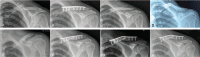

Open reduction and pre-contoured locking plate fixation is a popular treatment option for displaced midshaft clavicle fracture. Lag screw and cerclage are 2 main intraoperative techniques to reduce and fix fragments. However, both lag screw and metallic cerclage have disadvantages. The doubled-suture Nice knot has been reported in many areas of orthopedic surgery for its effectiveness. This study aims to compare the outcomes of comminuted mid-shaft clavicle fractures reduced by Nice knots vs traditional techniques (lag screw or/and metallic cerclage) when bridged with pre-contoured locking plates.We retrospectively reviewed 101 patients (65 females and 36 males) diagnosed with midshaft clavicle fractures with at least one wedge fragment reduced by either Nice knots or traditional methods and bridged with pre-contoured locking plates between December 2016 and April 2019. Operation time, functional outcomes, pain, patient satisfaction, fracture healing, and complications were assessed at a follow-up of 12 to 40 months.The mean age of all the patients was 50.8 years. There were 52 and 49 patients in the Nice knot group and traditional group respectively, and no differences between 2 groups were found in general patient characteristics, fracture type, follow up and injury-to-surgery duration. The Nice knot group had significant less operation time (P < .01) than the traditional group (mean and standard deviation [SD], 78.6 ± 19.0 compared with 94.4 ± 29.9 minutes, respectively). For healing time, functional score, pain, satisfaction and complications, there were no significant differences between groups, despite the Nice knot group had slightly better results.Both Nice knots and traditional methods treated for comminuted Robinson type 2B clavicle fractures were effective and safe. And the Nice knots seemed to be superior with significant less operation time.